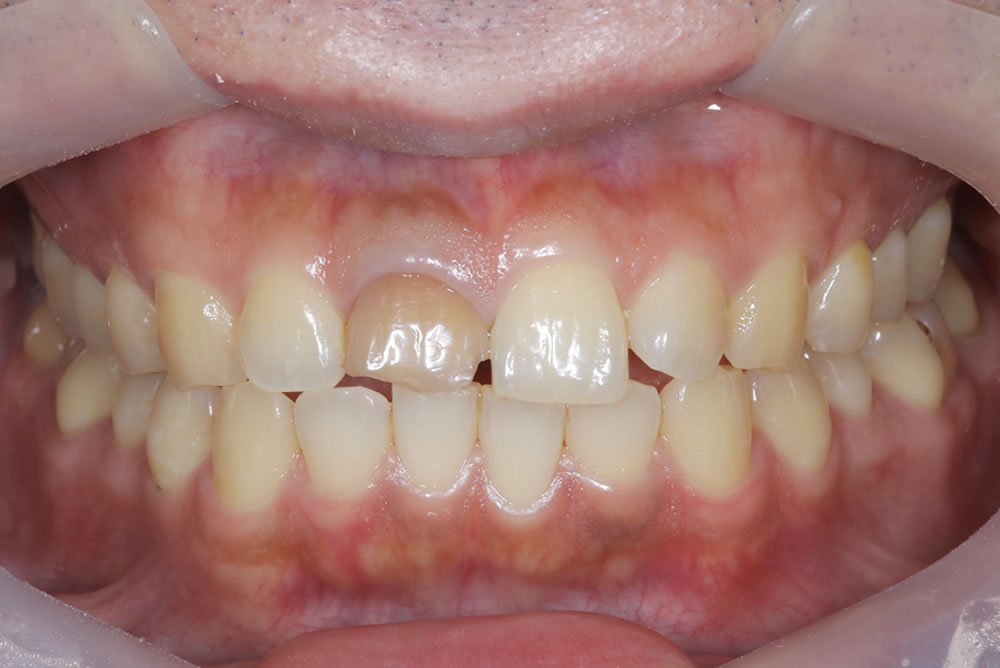

最終のインプラントの上部構造(ジルコニア)を装着

最終のインプラントの上部構造(ジルコニア)を装着し、咬み合わせを調整しました。

ホワイトニングで「口元全体」を仕上げる

前歯1本だけが綺麗でも、周囲の歯との色が合っていなければ違和感が残ります。

そこで、仮歯の期間中にホワイトニングを実施しました。口元全体のトーンを整え、「作った歯」ではなく「もともとこうだった」ような仕上がりを目指しました。